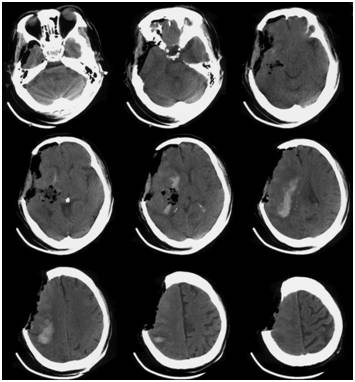

术后床旁移动CT复查头颅CT如Fig. 2所示,清除大部分血肿,少量血肿局部残留。复查血常规示:Hb104g/L,PLT50×109/L,HCT30.3%。给予脱水、抗感染、止血、神经保护、升血小板、营养支持等综合治疗,患者病情逐渐平稳。后出现肺部感染、上消化道出血等相关并发症,给予相应治疗后均好转。2017年2月16日右侧瞳孔对光反射恢复。2017年2月19日复查头颅CT示血肿基本吸收,中线结构无明显移位(Fig.3)。患者意识状态逐渐改善,于2月23日患者神志朦胧,可简单完成遵嘱动作。于2月27日出院,转当地医院康复治疗,出院一周后患者完全清醒,语言清,左侧偏瘫,左侧肢体肌力1-2级。

Fig.2术后复查头颅CT示血肿大部分被清除